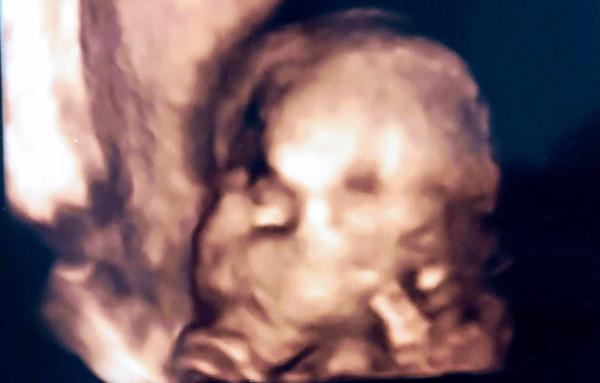

Velký nos na ultrazvuku. Máte zkušenost? A byl pak normální?

Ahoj, mám nevšední dotaz. Měli vaše miminka na fotkách z ultrazvuku velký nos a ve skutečnosti pak byl normální? Vím že mohou být ty ultrazvukové fotky zkreslené... Ano důležitější je, že je mimčo zdravé ❤️ jen mě to zajímá.

nam doktor rikal, ze pokud ma mlade na tom 3d ultrazvuku velkej nos, tak je to tim, ze pri snimani zaklonilo hlavu 🙂 ze maj jinak vsechny pidiknoflik

Mají často nos přimáčknutý, takže všelijaké patvary. Většina mimin má pidiknoflíčky pršáčky, konečný tvar se formuje po 3 letech.

Dcera měla na jednom utz místo nosu pěkný frňák a po narození po něm nebylo ani vidu. Má krásný nosík, tak se neboj. Utz muže zkreslovat ;)